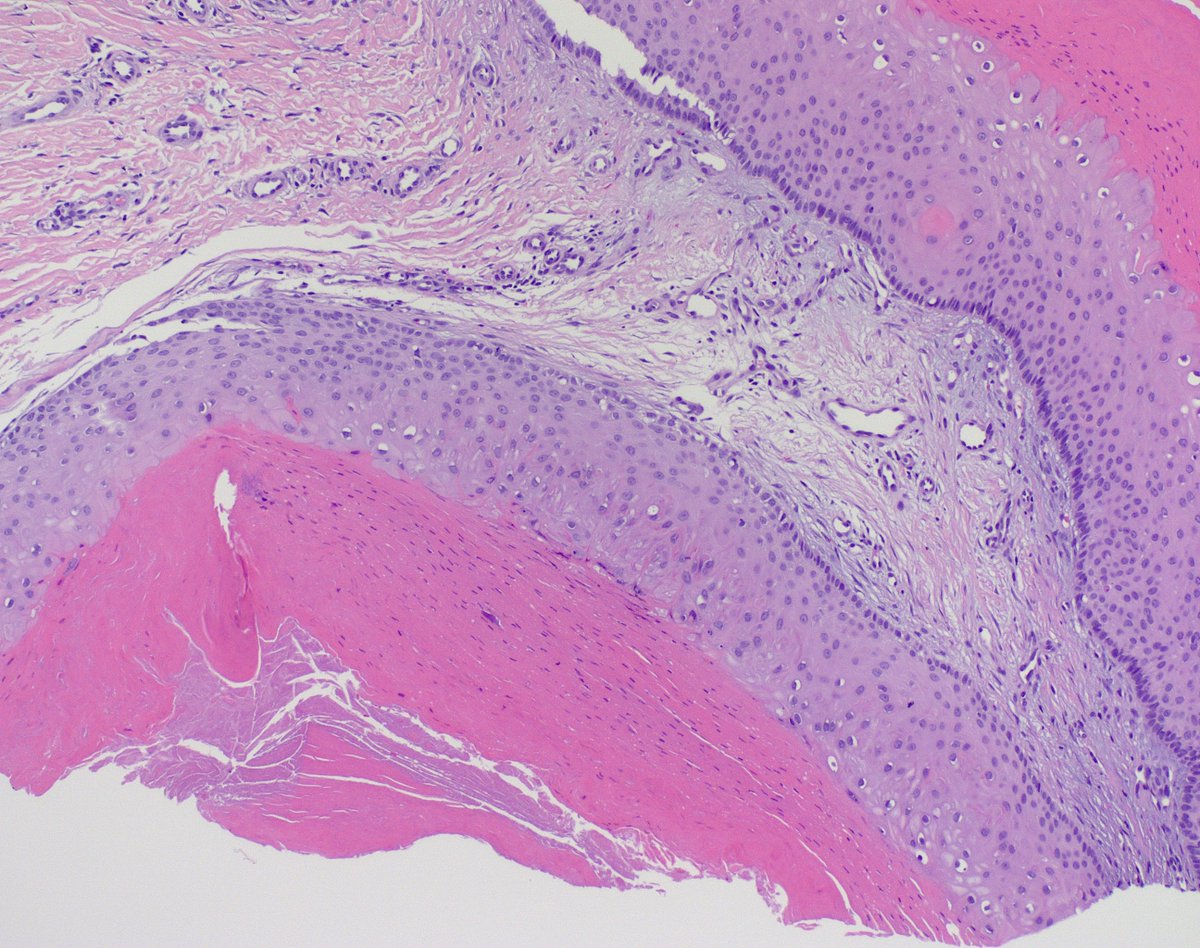

20s♂️ in good health, 4 months hx of 'cyst' axilla. Tons of eos, mostly in the dermis, also focally in the epidermis. Slam dunk persistent/exuberant arthropod 'bite', or something else? What would you include in the ddx? Ty! Tim McCalmont Henry YANG Dermpath_doc_trish Diego Morales, MD Etan Marks, DO

20s♂️ in good health, 4 months hx of 'cyst' axilla.

Tons of eos, mostly in the dermis, also focally in the epidermis.

Slam dunk persistent/exuberant arthropod 'bite', or something else?

What would you include in the ddx? Ty!